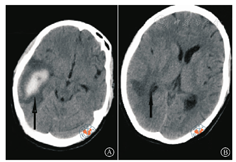

产科、重症监护科和神经外科联合会诊后转入神经外科进行专科治疗,予降压、止血、降颅内压、纠正低蛋白血症、输血、护肝、抗感染等治疗后患者病情控制平稳,各项检查指标逐渐恢复正常。4月19日行脑部CT及CT血管造影检查,提示右侧颞叶血肿,左蛛网膜下腔出血,鼻中隔偏曲。结合患者4月8日脑部CT检查结果,患者颅脑血肿较前稍吸收(图2,图3)。患者于剖宫产术后28 d康复出院,无明显神经系统功能障碍。出院诊断:(1)HELLP综合征并发脑出血;(2)孕5产2,妊娠34+2周,剖宫产;(3)重度子痫前期;(4)胎儿窘迫;(5)中央型前置胎盘;(6)羊水偏少。出院后3个月余电话随访,患者出院后血压维持在110~130/75~90 mmHg,术后3个月外院复查脑部CT颅脑血肿较前吸收(具体报告单未见),无神经系统功能障碍后遗症,新生儿生长发育良好。